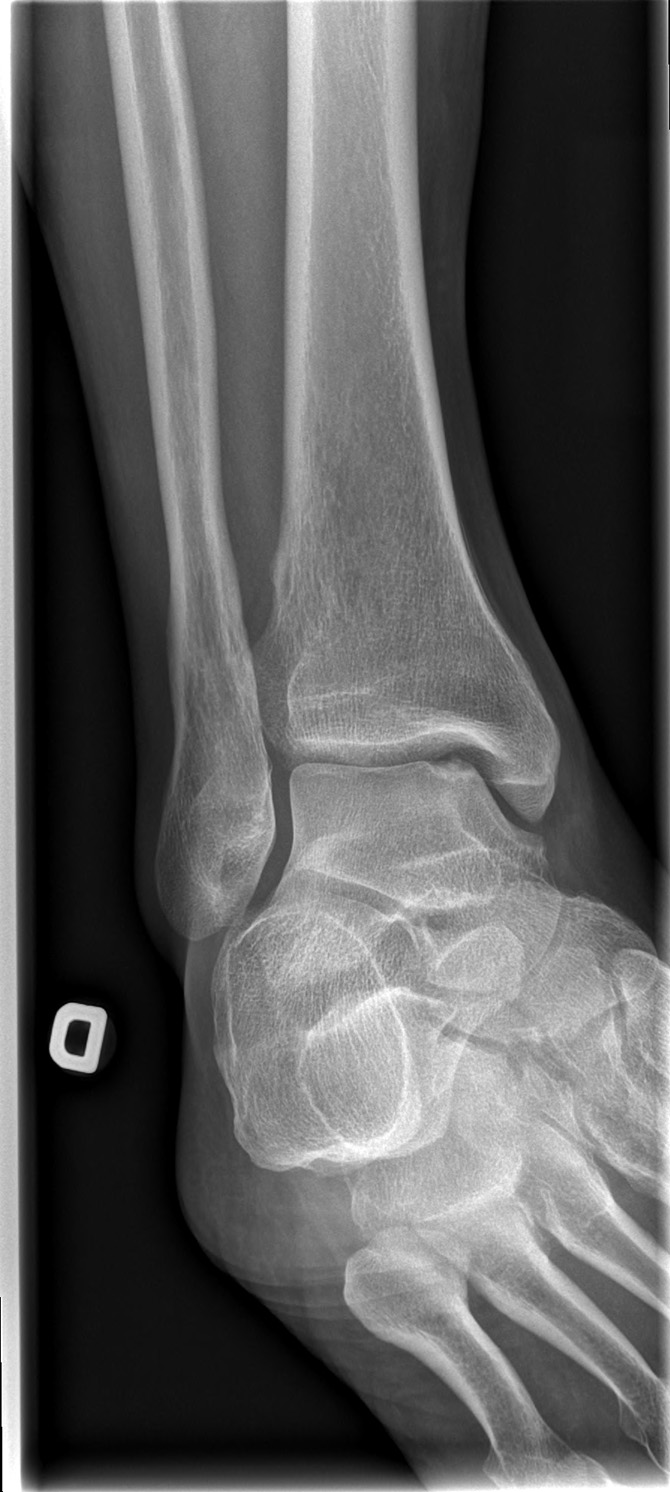

69-year-old male:

Persistent right ankle pain following a sprain.

Osteochondritis dissecans

Cortical defect and sclerosis of the superomedial talus compatible with an osteochondral lesion. Assessment of the fragment is impossible on these views, however, and the precise type cannot be acertained.